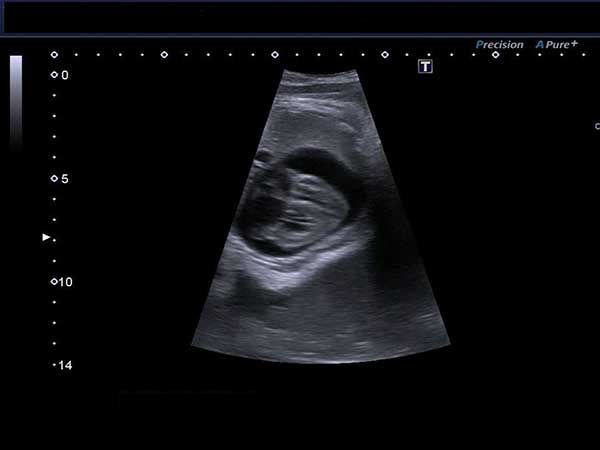

A 40-year-old woman reports a 20-week history of amenorrhea. What is your diagnosis based on these images?